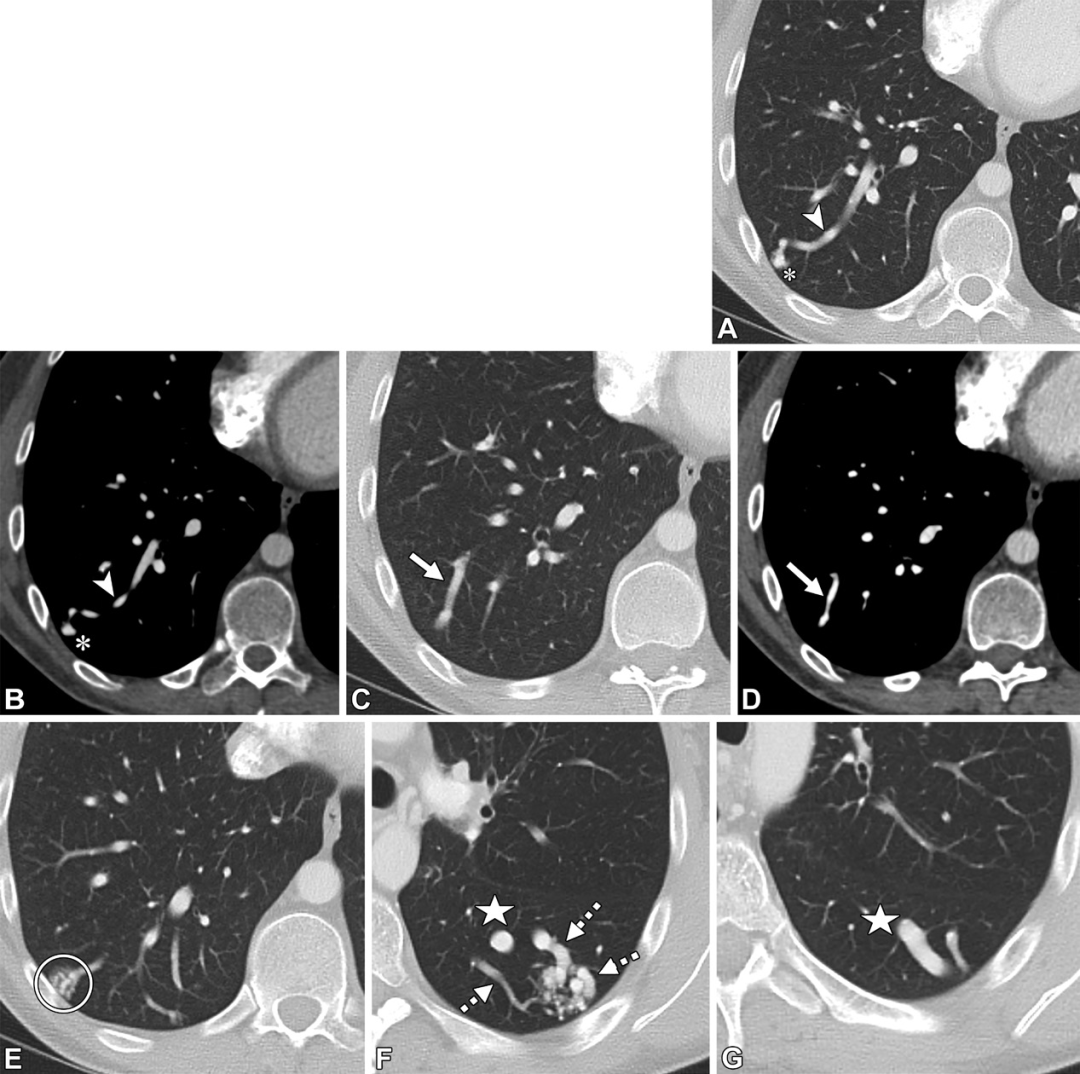

PAVM。轴位CT图,32岁男性,遗传性出血性毛细血管扩张症,因右向左分流导致的慢性低氧血症。(A,B)轴位CT图,可见右肺下叶PAVM的病灶(白色信号)及引流静脉(白色箭头)。(C,D)轴位CT图,可见供血动脉大于3mm(白色箭头)。(E)右肺下叶另见一个PAVM,在供血动脉及引流静脉之间的磨玻璃密度影(白色圆圈),提示显微镜下毛细血管扩张。(F,G)一个复杂的PAVM位于左肺下叶,可见三个供血动脉(F图中白色虚线箭头)以及一个粗大的引流静脉(白色星号),注意观察引流静脉比供血动脉大。